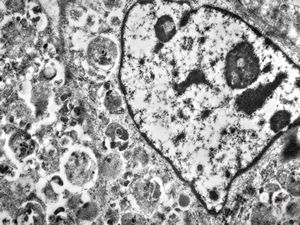

normal seromucinous salivary gland